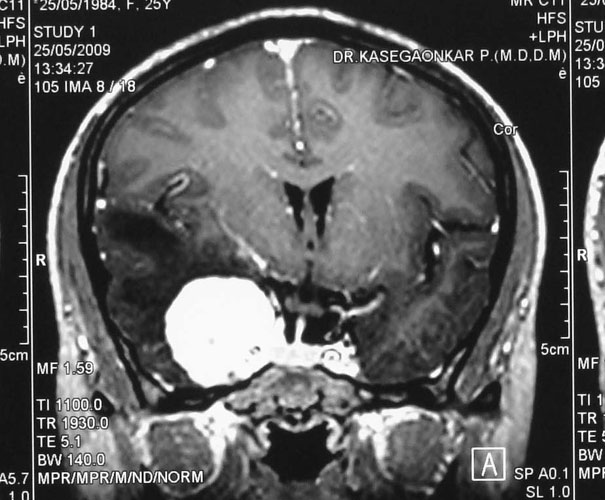

Intracranial Meningiomas

Meningiomas are solid, nodular (rarely, cystic), benign tumors that arise from the coverings of the brain, and compress the adjacent brain tissue. Usually present with headache, visual disturbances or weakness of half of the body. Diagnosis is by progression, especially if the tumor removal has been incomplete. Diagnosis is by MRI and surgery is curative.